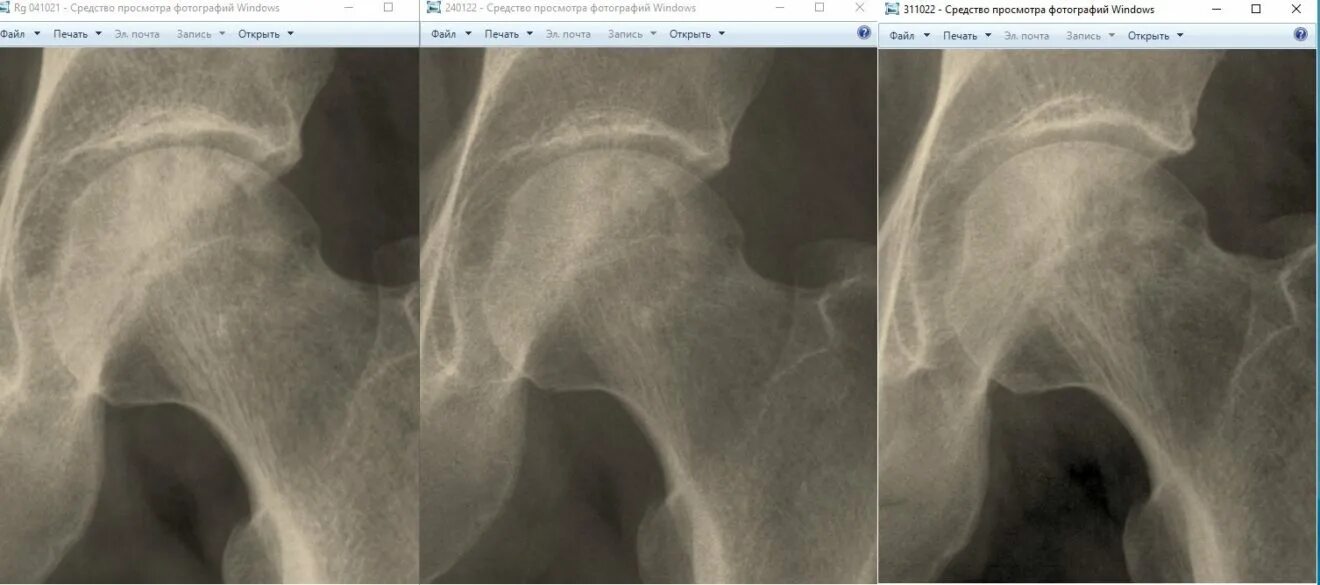

Асептический некроз тазобедренного сустава лечение без операции